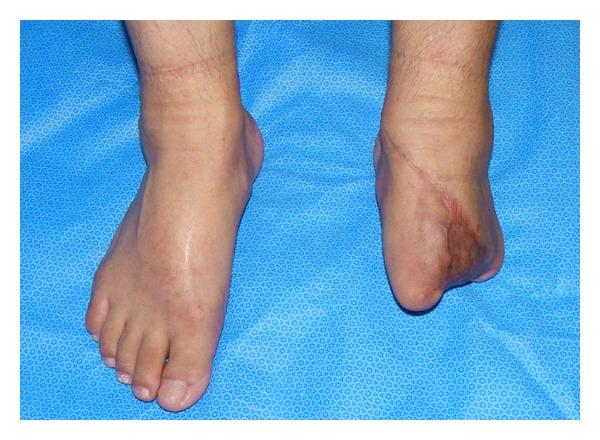

Malignant peripheral nerve sheath tumor (MPNST) is a rare high-grade soft tissue sarcoma. The epithelioid variant accounts for 5% or less of MPNSTs; the clinical behavior of this variant is unclear. Reports of approximately 40 cases are available in the English literature; however, most reports addressed clinicopathological features rather than therapeutic procedures or clinical courses. We describe a case of a 62-year-old male with an epithelioid MPNST of the left foot. Multiple lung metastases developed after radical surgery on the primary lesion. The response to adjuvant chemotherapy including doxorubicin and ifosfamide was favorable, and thoracoscopic resection was subsequently performed on the remaining three metastases. No evidence of recurrence or metastasis was observed at the 12-month followup after the first operation. Further followup and chemotherapy may be required.

摘要

恶性外周神经鞘膜瘤(MPNST)是一种罕见的高级别软组织肉瘤。上皮样变体占MPNST的5%或更少;该变体的临床行为尚不清楚。英文文献中有大约40例相关报道;然而,大多数报道关注的是临床病理特征,而非治疗方法或临床病程。我们描述了一例62岁男性,患有左足上皮样MPNST。原发灶根治性手术后出现了多发肺转移。对包括阿霉素和异环磷酰胺在内的辅助化疗反应良好,随后对其余三处转移灶进行了胸腔镜切除术。首次手术后12个月的随访未发现复发或转移迹象。可能需要进一步随访和化疗。